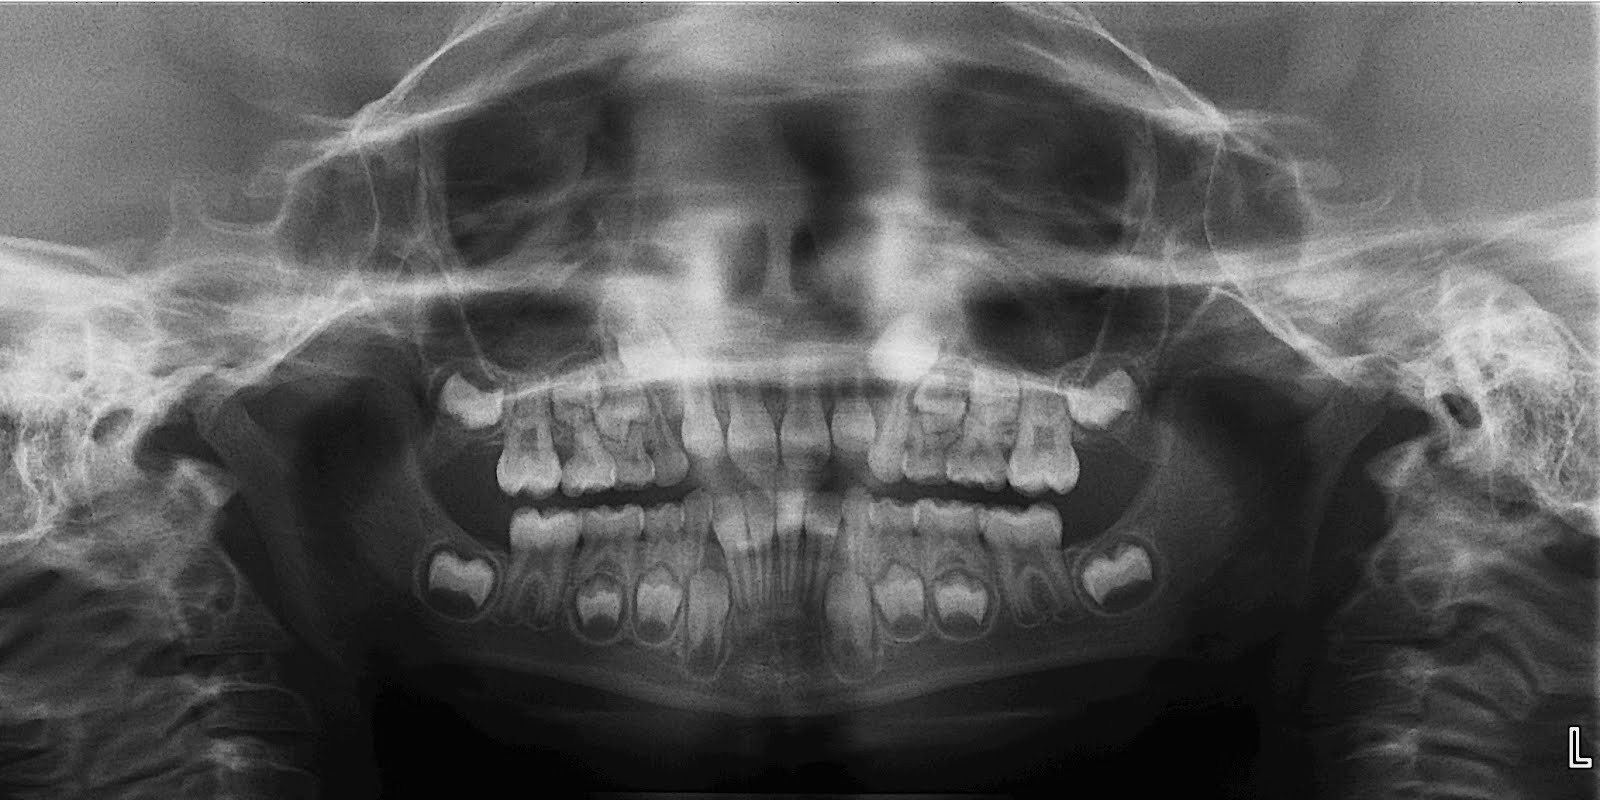

BiggsHansen Orthodontics Smiles Above the Rest Dental Radiograph Orthodontic Exposure It is also recommended to upright the second molar with the removal of the impacted third molar. surgical exposure of these impacted teeth is accomplished using an open or closed surgical procedure. Diagnosing and localizing the impacted tooth/teeth, establishing a. orthodontic treatment followed by surgical exposure of the canine to bring. keys to realizing excellent outcomes include:. Orthodontic Exposure.